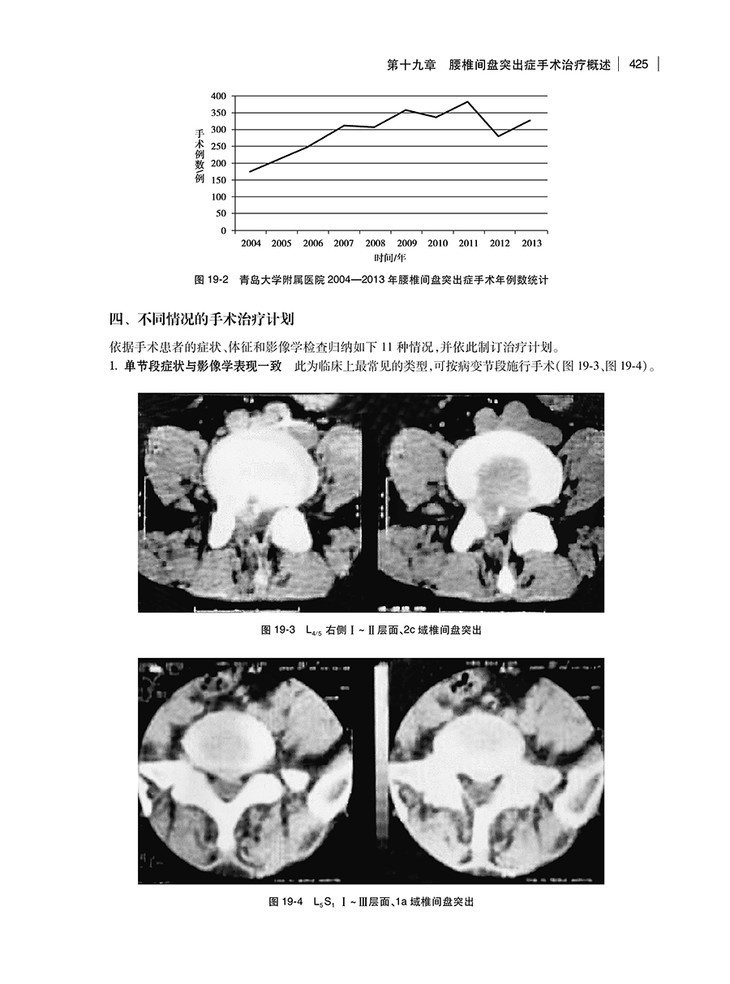

第十九章 腰椎间盘突出症手术治疗概述